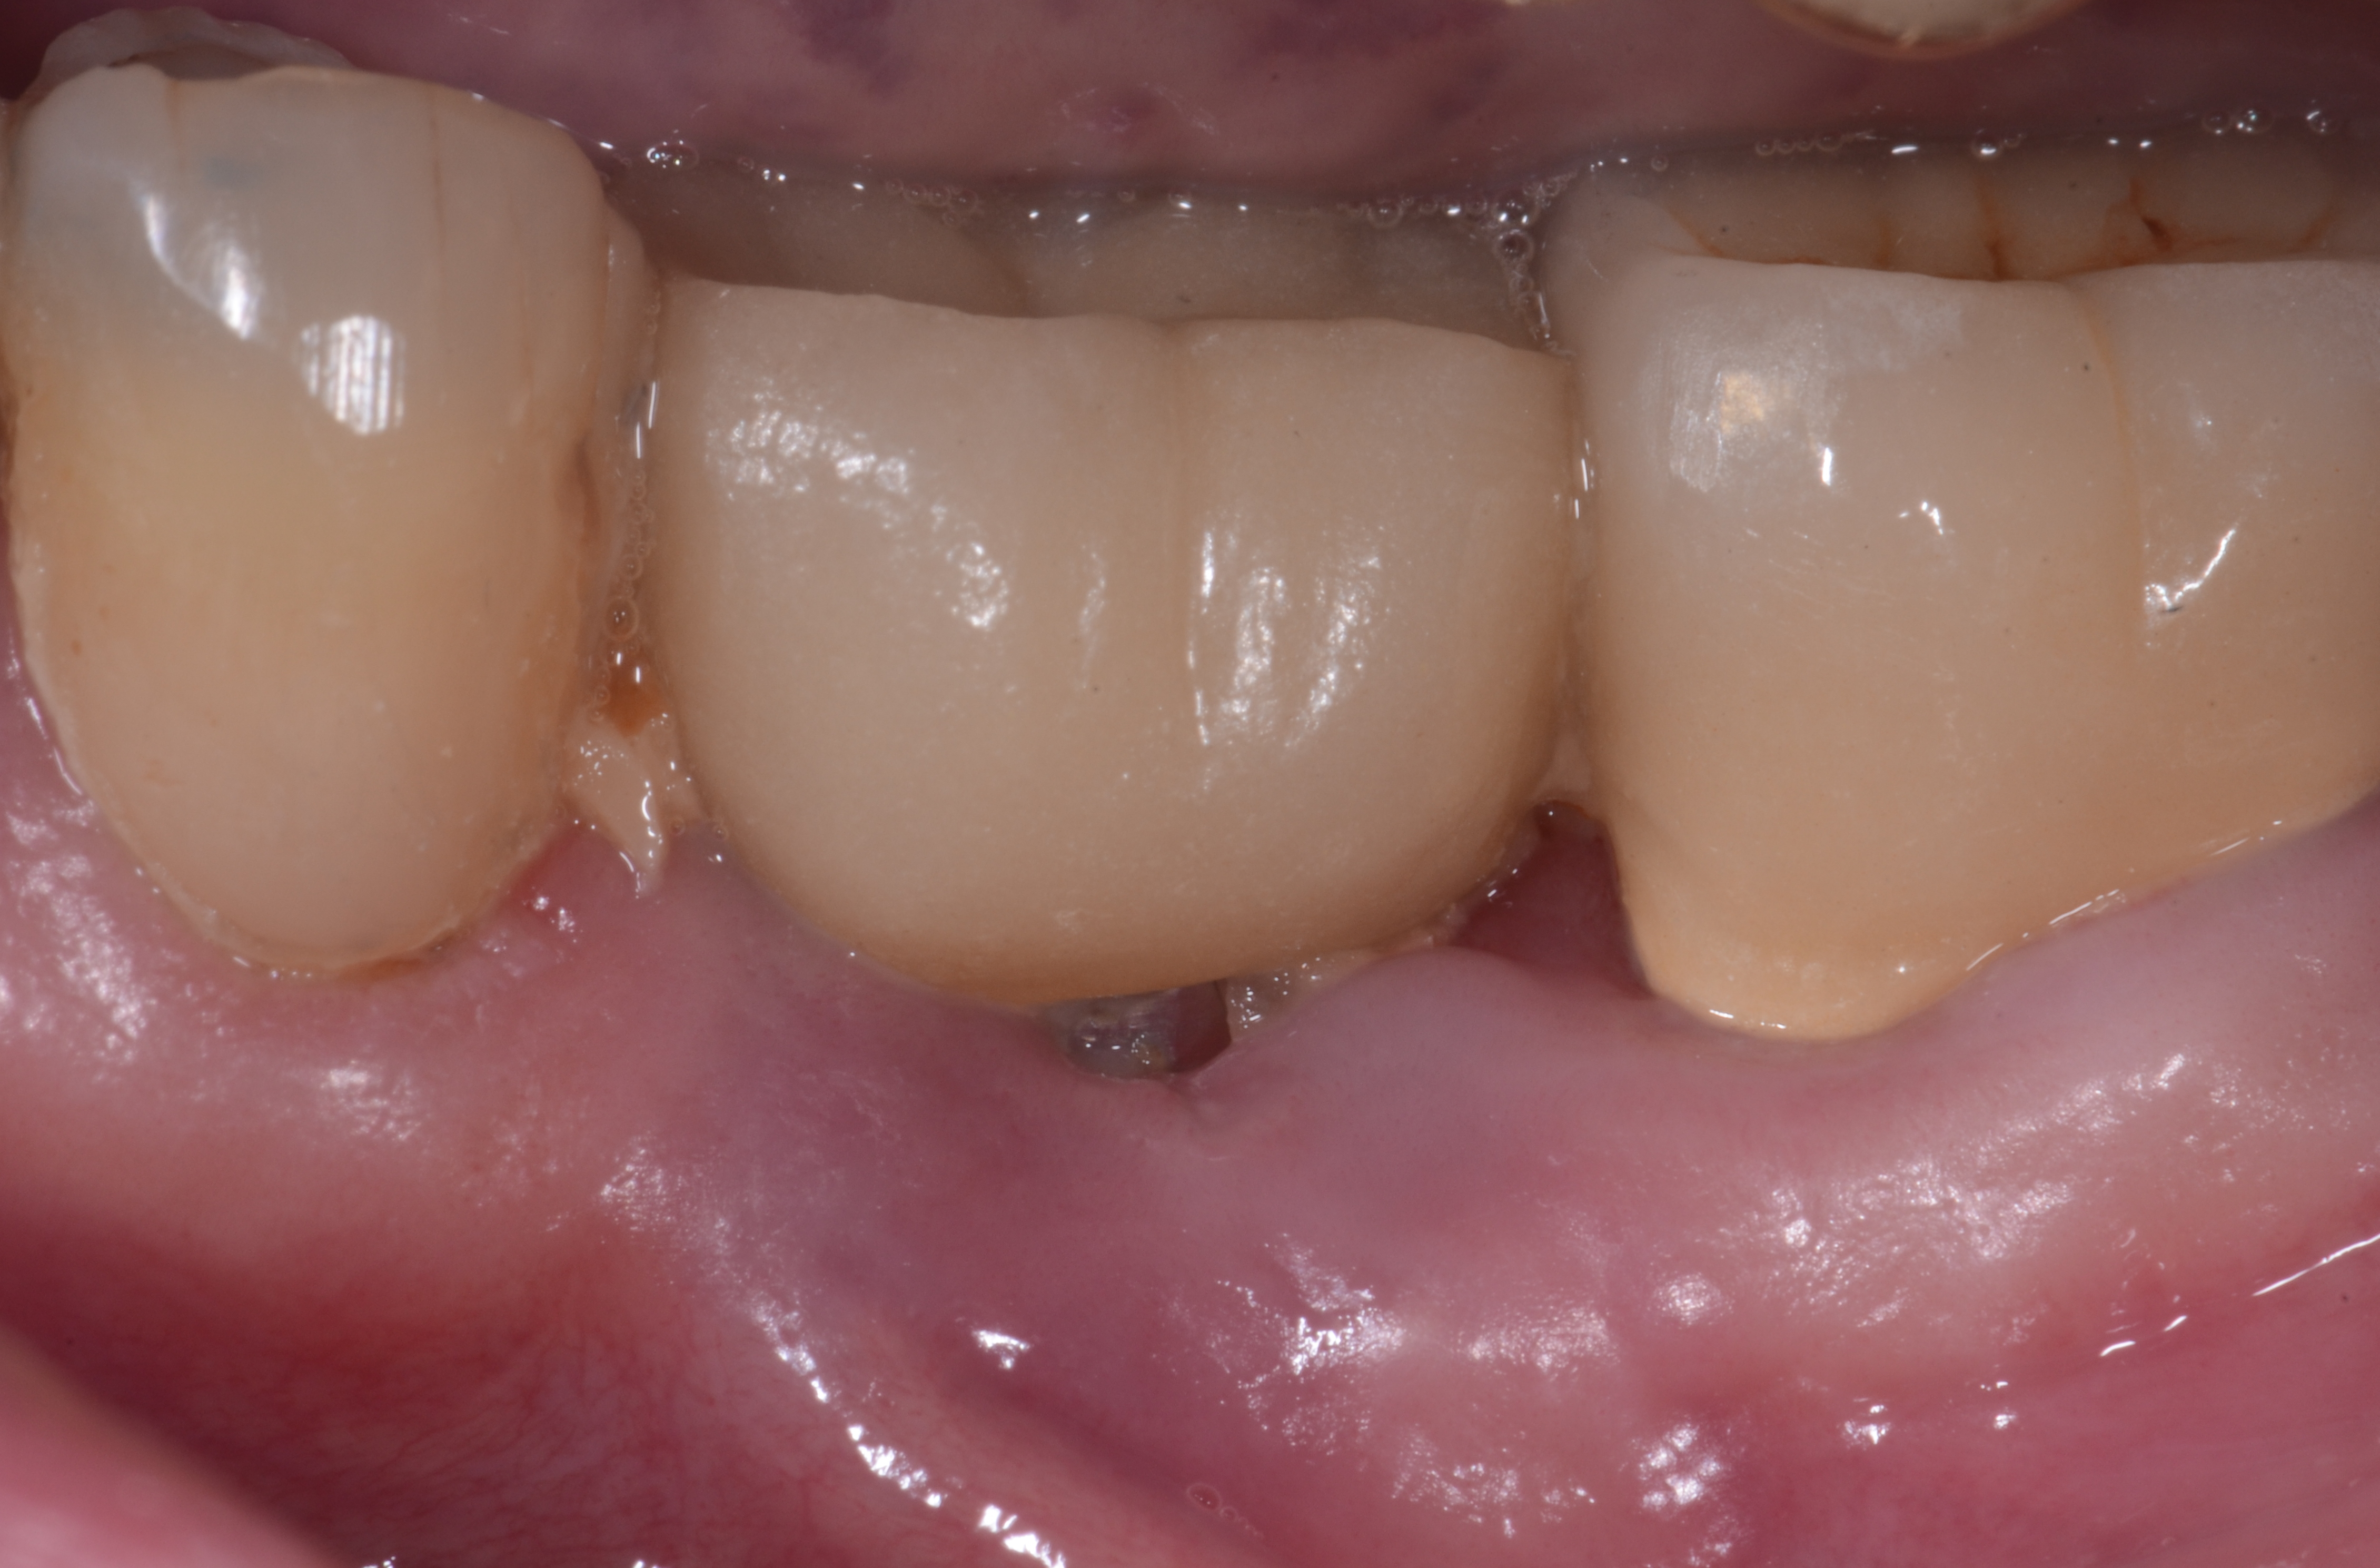

Fig 3. Clinical view of a mandibular left first molar in an 84-year-old patient with a peri-implantitis lesion. The implant had been healthy for the previous 5.5 years.

Figure 3

Fig 4. A radiograph of the area suggests the advanced nature of this lesion.

Figure 4